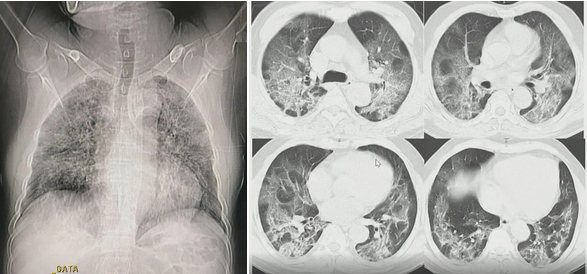

TS Lưu cung cấp hình ảnh X-quang phổi của BN867 được chụp hôm 9/8 - 9 ngày sau khi có biểu hiện bệnh. Hình ảnh cho thấy tổn thương phổi lan tỏa hai bên, chứng tỏ bệnh nhân bước vào giai đoạn đỉnh bệnh. Ngoài tình trạng kính mờ, phổi bị ảnh hưởng tạo hình tổ chức kẽ, lưới rõ rệt.

Hình ảnh X-quang và cắt lớp vi tính phổi của bệnh nhân 867. Ảnh: Bệnh viện Đại học Y Hà Nội.

Phân tích hình ảnh cắt lớp vi tính, TS Lưu cho hay chúng rất điển hình ở bệnh nhân Covid-19 với kính mờ, phổi đông đặc, nằm ở các dải dưới màng phổi. Tổn thương phổi rất nặng, chiếm hơn 75% nhu mô.

“Nếu có bệnh nền đi kèm, người này có tiên lượng rất nặng”, TS Lưu nhận định đồng thời nhấn mạnh những người có tổn thương nhu mô phổi chiếm hơn 50% được xếp vào nhóm nguy cơ nặng về hô hấp.

Xem xét X-quang phổi của BN867, TS Lưu cho biết người này xét nghiệm rRT-PCR lần một âm tính nhưng với tổn thương phổi điển hình có thể khẳng định nguy cơ mắc Covid-19 rất cao. Các bác sĩ cần chú ý để phát hiện người mắc Covid-19, kể cả khi họ âm tính với SARS-CoV-2.